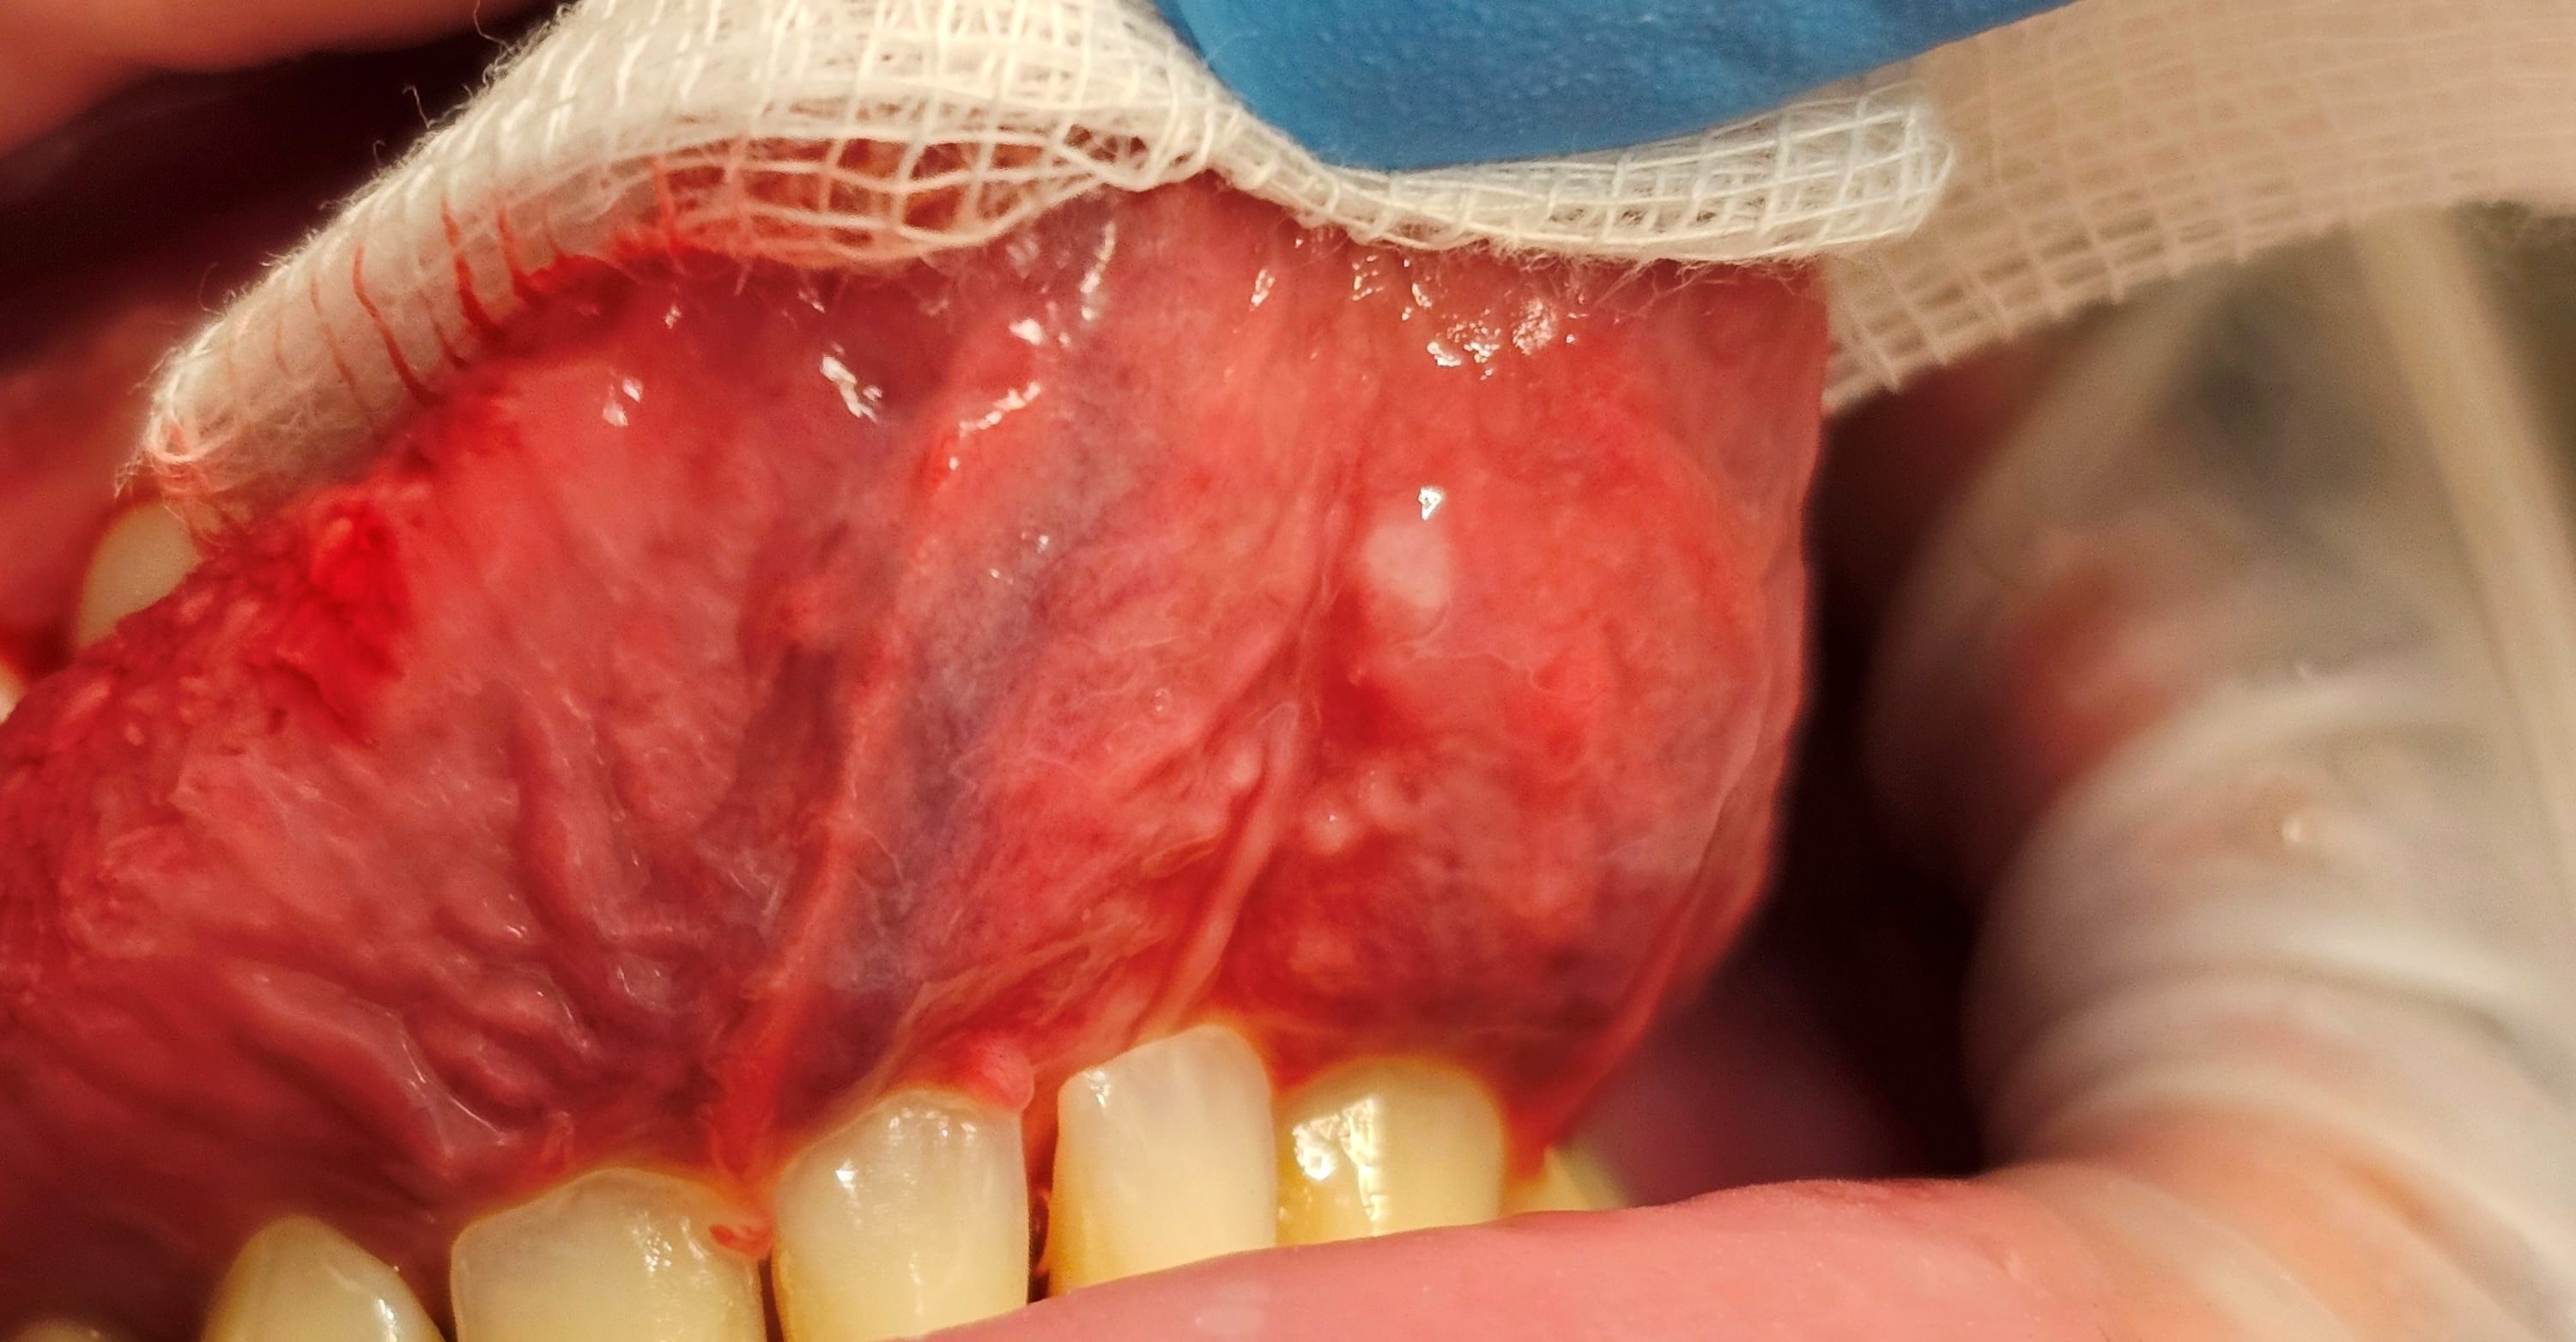

35 ans, non fumeur, hygiène moyenne, qui présente une image qui me pose question:

Lorsqu'il mange très salé, il à une "bulle" dans la région pelvilinguale, semble t il gonflement rempli de liquide, il me dit que qu'elle disparait en 1 jours, et que si il la perce, impression que de" l'eau" s'écoule et disparait dans la journée aussi.

Mon problème, à la palpation, je trouve la zone blanche,(environ 2 à 3 mm de diamètre) dure mais non douloureuse.

Photos avec le téléphone, je n'avais pas le canon.

C’est un simple kyste mucoïde pour moi.

Kyste glande salivaire accessoire

oui mais en principe, à la palpation pour un kyste mucoïde , la tuméfaction est de consistance molle et mobile par rapport au plan profond. La palpation des aires ganglionnaires est sans anomalie notable, pour un kyste mucoïde, ici c'est "dur" et non mobile.

pour moi aussi c est un mucocele

Idem, mucocele visuellement. Pour en avoir eu un en personne (labial), c'est très tendu et pas si mou que ça finalement, rien à voir avec l'aspect mou fluctuant d'un abcès collecté.

Plutôt la consistance souple élastique d'un ganglion.

c'est la zone blanche qui est dure à la palpation,pas les zones ganglionnaire.

c'est ce coté "dur" non douloureux qui me fait hésiter sur le diagnostic

Pour moi ça colle. Avec le temps ca devient un peu "fibreux" comme consistance, ce qui explique cette sensation ferme.